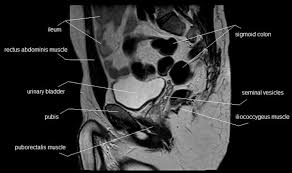

Pelvis Muscles Mri Anatomy / The Pelvis Ct Anatomy Mp4 Youtube - Pelvic wall muscles include the anterior and inferior obturator internus, and the posterior iliacus, piriformis, and psoas major (figures 8 and 9).

Pelvis Muscles Mri Anatomy / The Pelvis Ct Anatomy Mp4 Youtube - Pelvic wall muscles include the anterior and inferior obturator internus, and the posterior iliacus, piriformis, and psoas major (figures 8 and 9).. Conclusions • the primary imaging modalities for the abdomen and pelvis are plain film, ultrasound, and ct. 48 adductor longus muscle this muscle is the most. Key facts about the muscles of the pelvic floor. A pelvis mri (magnetic resonance imaging) scan is an imaging test that uses a machine with powerful magnets and radio waves to create pictures this mri pelvis cross sectional anatomy tool is absolutely free to use. The pelvis and the pelvic floor muscles seal the abdominal and pelvic cavity in a caudal direction;

The majority of the time, these muscular tissues are quite solid and also are able to support the pelvic bone. The muscle originates from the body of the pubis and attaches to the pectineal line and proximal part of the linea aspera of femur. The pelvic diaphragm is composed of the ischiococcygeus muscle and levator ani muscle, the latter of which consists of the iliococcygeus, puborectalis, and pubococcygeus muscles. Anteriorly, pubocervical fibromuscularis is attached to the levator ani using arcus tendineus fascia pelvis (fig. The pelvis and the pelvic floor muscles seal the abdominal and pelvic cavity in a caudal direction;

The pelvic diaphragm is composed of the ischiococcygeus muscle and levator ani muscle, the latter of which consists of the iliococcygeus, puborectalis, and pubococcygeus muscles. Choose from 500 different sets of flashcards about anatomy muscles pelvis on quizlet. If these muscular tissues end up being weak. Use the mouse scroll wheel to move the images up and down alternatively use the tiny arrows (>>) on both side of the image to move the images.>>) on both side of the image to move the images. Use the mouse scroll wheel to move the images up and down alternatively use the tiny arrows (>>) on both side of the image to move the images.>>) on both side of the image to move the images. Key facts about the muscles of the pelvic floor. Case contributed by assoc prof craig hacking. A pelvis mri (magnetic resonance imaging) scan is an imaging test that uses a machine with powerful magnets and radio waves to create pictures this mri pelvis cross sectional anatomy tool is absolutely free to use.

The pelvic floor muscles, which are located in the pelvic outlet, make up the pelvic diaphragm, which separates the pelvic viscera from the more inferior perineal structures.